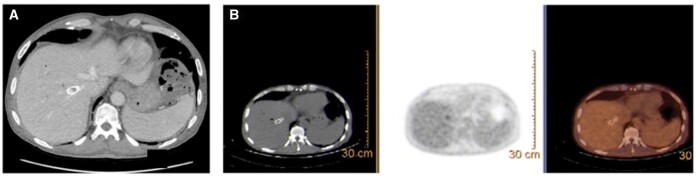

Transjugular intrahepatic portosystemic shunting (TIPS) is an established strategy for the management of complications of portal hypertension. Endoprosthetic infection ("endotipsitis") is a rare but serious and difficult-to-treat complication of TIPS placement. Here we report the occurrence of an infected thrombus complicating TIPS placement in a patient with extra-hepatic portal vein obstruction, recurrent variceal bleeding and portal biliopathy accompanied by recurrent cholangitis. Infected thrombotic material within TIPS could be removed only by employing rotational thrombectomy. This procedure revealed the presence of a biliary fistula which carried pathogens in the systemic circulation. The multiple episodes of sepsis did no longer recur following exclusion of the biliary fistula. This case highlights the possibility to use rotational thrombectomy for the management of complex cases of TIPS dysfunction.